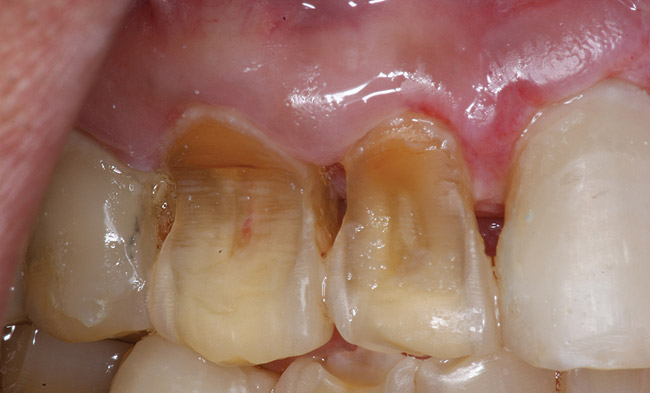

If a patient has risk factors that can contribute to dental erosion, an examination will reveal clinical signs and symptoms of dental erosion. It is unlikely that dental erosion will be seen without other contributing factors. Tooth wear and abrasion typically occur in combination with dental erosion. In the clinical evaluation of tooth surfaces for the diagnosis of erosion, what is typically seen are smooth, shiny surfaces of the teeth where the usual anatomic form of the tooth should be. In patients ingesting very acidic diets, the facial surfaces of anterior teeth are very smooth, and if the beverages being ingested have high sugar content, these teeth may have caries at their facial gingival margins (Figure 1). The occlusal surfaces of posterior teeth in the more advanced stages of erosion due to regurgitation may have extensive exposed dentinal areas with loss of anatomic form (Figure 2). In some cases, the chemical erosion combined with toothbrush–toothpaste abrasion can remove all the enamel, leaving only the dentin exposed (Figure 3). These teeth may exhibit sensitivity. Posterior teeth with restorations may demonstrate fillings that are higher than the surrounding occlusal surfaces of the enamel. Anterior teeth may demonstrate more incisal translucency due to tooth loss at the incisal edge. In patients with the eating disorder bulimia nervosa, who vomit, the hydrochloric acid causes extensive damage to the lingual surfaces of the anterior teeth, where the enamel is lost, leaving exposed dentin (Figure 4).

Figure 1  This patient had a history of drinking five to six bottles of an acidic carbonated beverage a day, leading to combined dental erosion–caries.

Figure 1